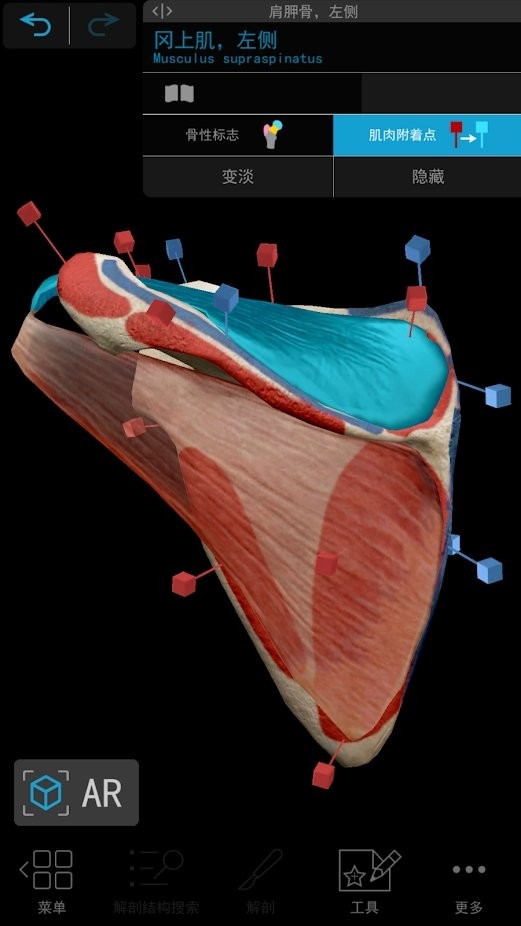

#2021人体解剖图谱 截图